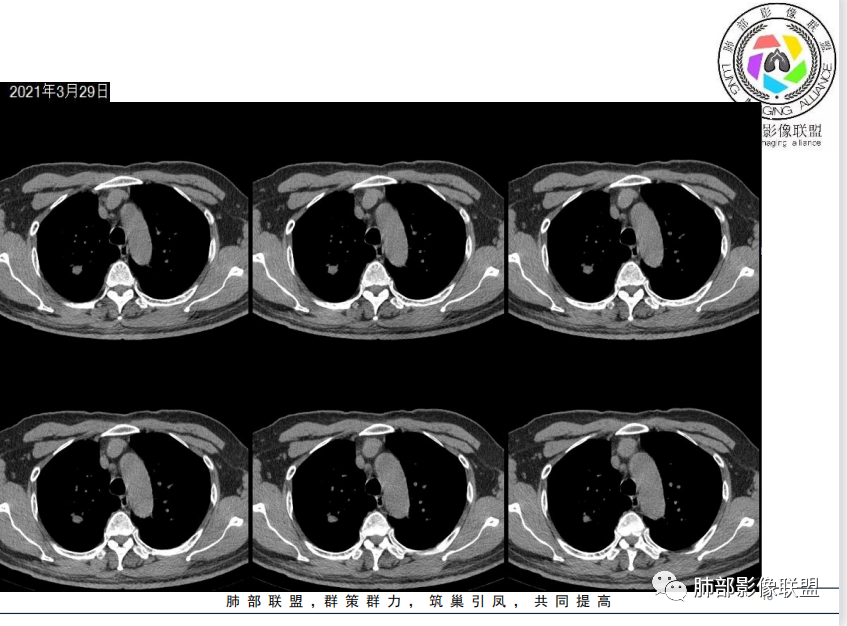

1、老年男性,4天前受凉后咳嗽、咳痰伴胸痛。

2、既往高血压史、吸烟史。

胸片提示右下肺感染

影像上似有马赛克灌注,提示小气道炎症可能